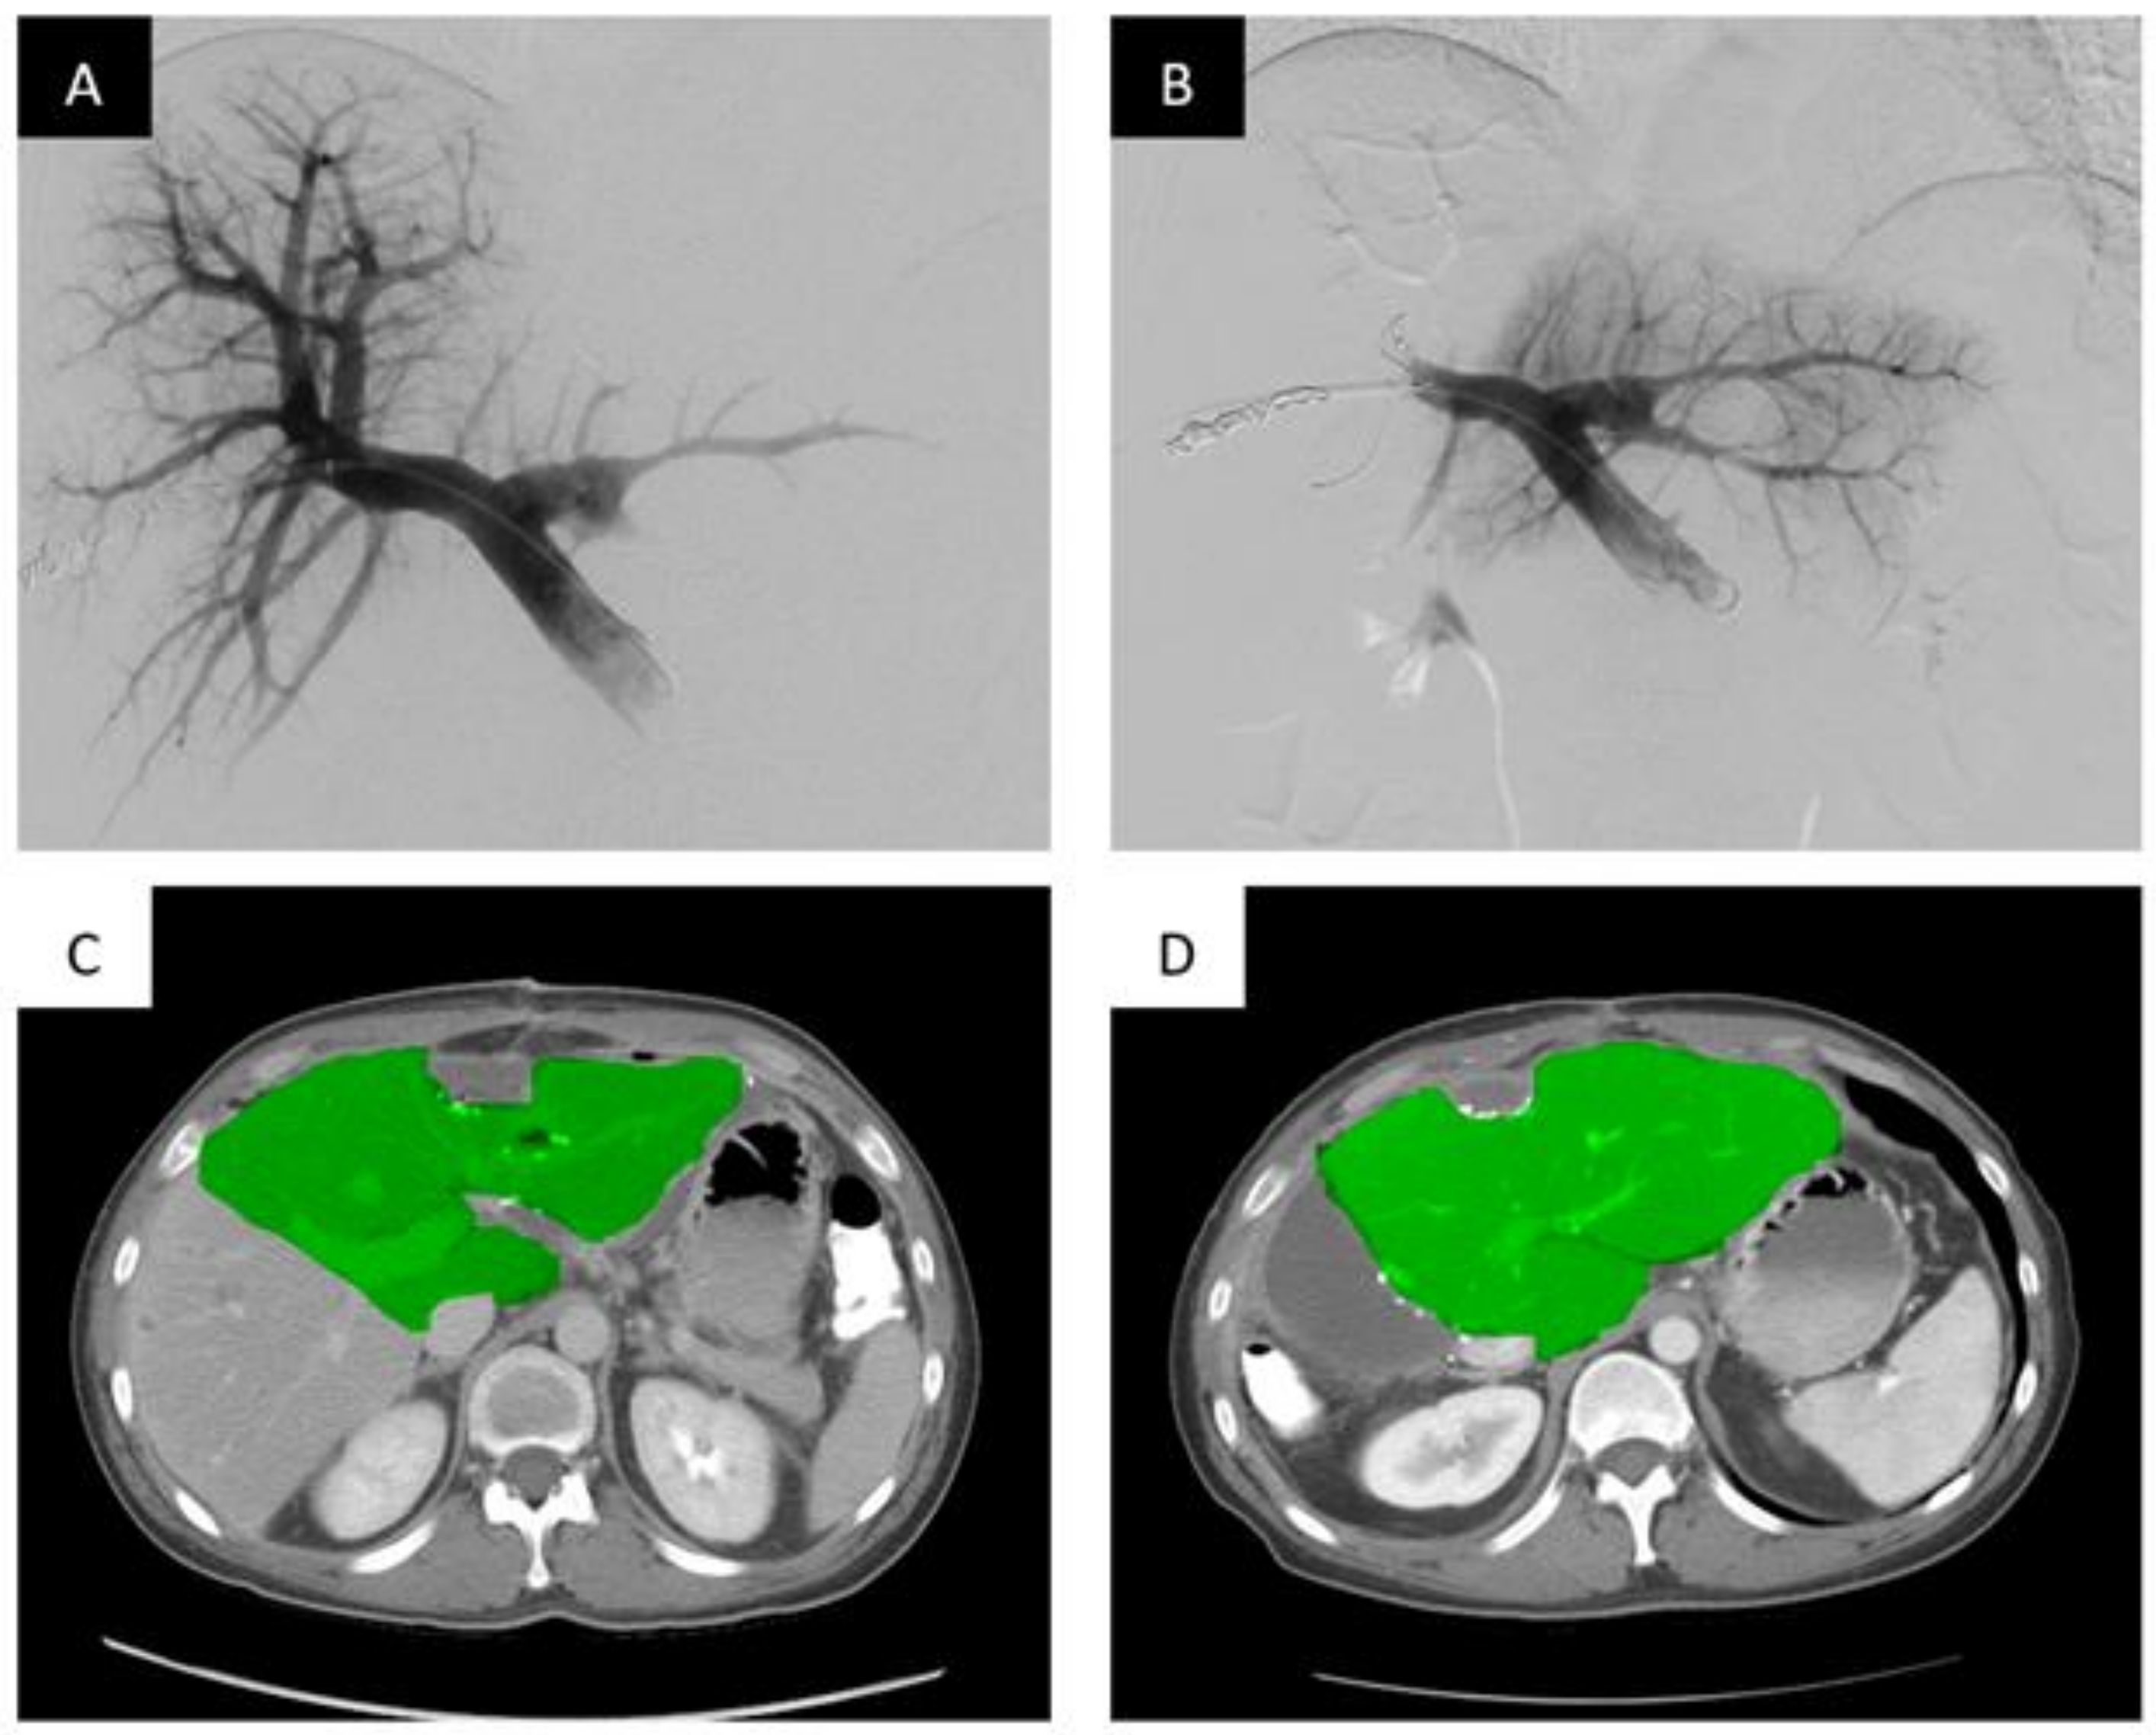

PVA particles/microparticles range in size from 150–1000 um and are widely commercially available for use. Because of their varying sizes, they are an excellent option for distal embolization. Typically, operators will use these particles in combination with coils or plugs for proximal embolization to provide complete embolization of the target portal veins (Figure 1).

Portal vein embolization of the right portal vein branch with PVA particles and coils demonstrates FLR hypertrophy. Portal vein embolization (PVE) of the right hepatic portal vein with PVA particles and coils. (A) Digital subtraction portography prior to embolization via access of the posterior division of the right portal vein. (B) Post-embolization single shot image of the right portal system embolized with PVA particles and a Nester coil (Cook Medical, Bloomington, IN, USA). (C) Axial contrast enhanced computed tomography (CT) slice demonstrating the pre-embolized liver, with the non-hypertrophied left lobe highlighted. (D) Post-PVE contrast-enhanced axial CT slice demonstrating noticeable hypertrophy of the left liver post-right PVE and hepatectomy (approximately 28 days post-resection).

In study by Camelo et al., 63 patients who received preoperative PVE with PVA particles and coils demonstrated an FLR increase from a mean value of 484 mL ± 242 to 654 mL ± 287 (p < 0.001), a mean percentage increase of 40% [38]. It should be noted that this study found a negative relation between the FLR volume before PVE and the FLR volume increase induced by PVE (R = −0.46, p < 0.001). Two out of the 64 patients (3.1%) suffered major adverse events. Ultimately, 44 patients underwent successful surgical resection (68.8%), with only one with postoperative hepatic insufficiency.